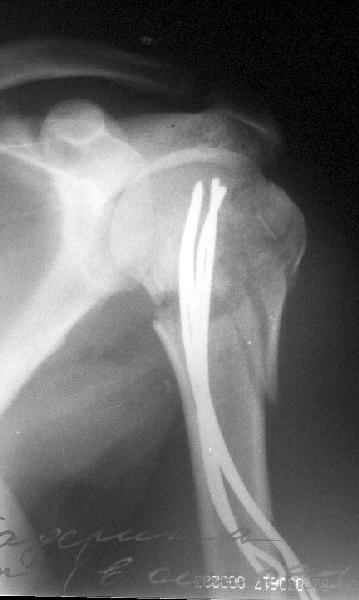

Здесь случай перелома-вывиха плеча, больному 56 лет, после "дважды" закрытой неудачной репозиции, опять же ургентно взяли в операционную, после полного общего обезболивания попытались сделать репозицию, и фиксацию провели спицами.

Больной находился в повязке, примерно напоминяющей косыночную, рекомендованы движения в локтевом суставе и маятниковые движения в плече, спицы удалены в три недели (были случаи миграции)

Просмотрел приложенный снимок пенетрации спиц в сустав. Мне кажется, здесь были некоторые отклонения от рекомендованного доктором Лазаревым варианта. Метод называется "фиксация напряженными спицами", т.е после внедрения в головку концы спиц расходятся! А следующий фиксатор укрепляет позицию, удерживает от смещения! Поэтому, чем больше спиц, тем лучше создается жесткость и это предупреждает миграцию.

В Вашем случае получилась обычная фиксация спицами, т.е. спицы вошли в головку параллельно и не раздвинулись! В прошлом примеры идеальной установки напряженных спиц, кроме доктора Лазарева, показал Женя Чекашкин из Намибии.